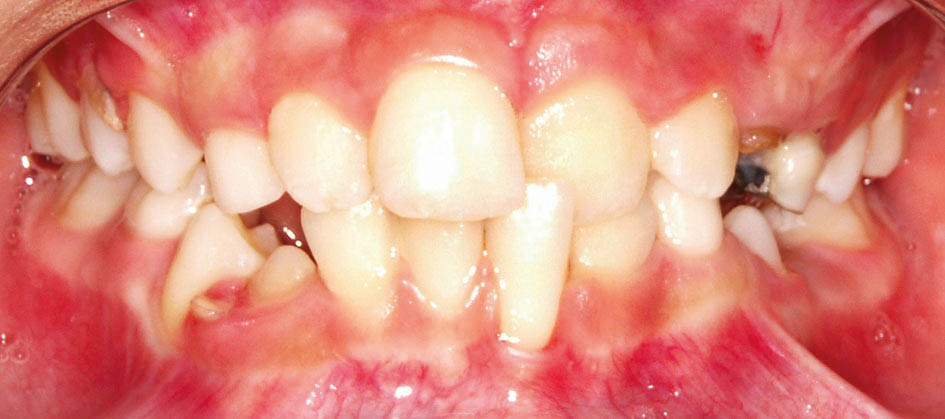

شکل 19-5: دیستال E پائین جلوتر از دیستال E بالاست، لذا بیمار در آینده کلاسIII میشود

شکل 20-5: دیستال E پائین عقبتر از دیستال E بالاست، لذا بیمار در آینده به احتمال زیاد کلاسII میشود

شکل 21-5: دیستال دندانهای E بالا و پائین در یک راستا هستند